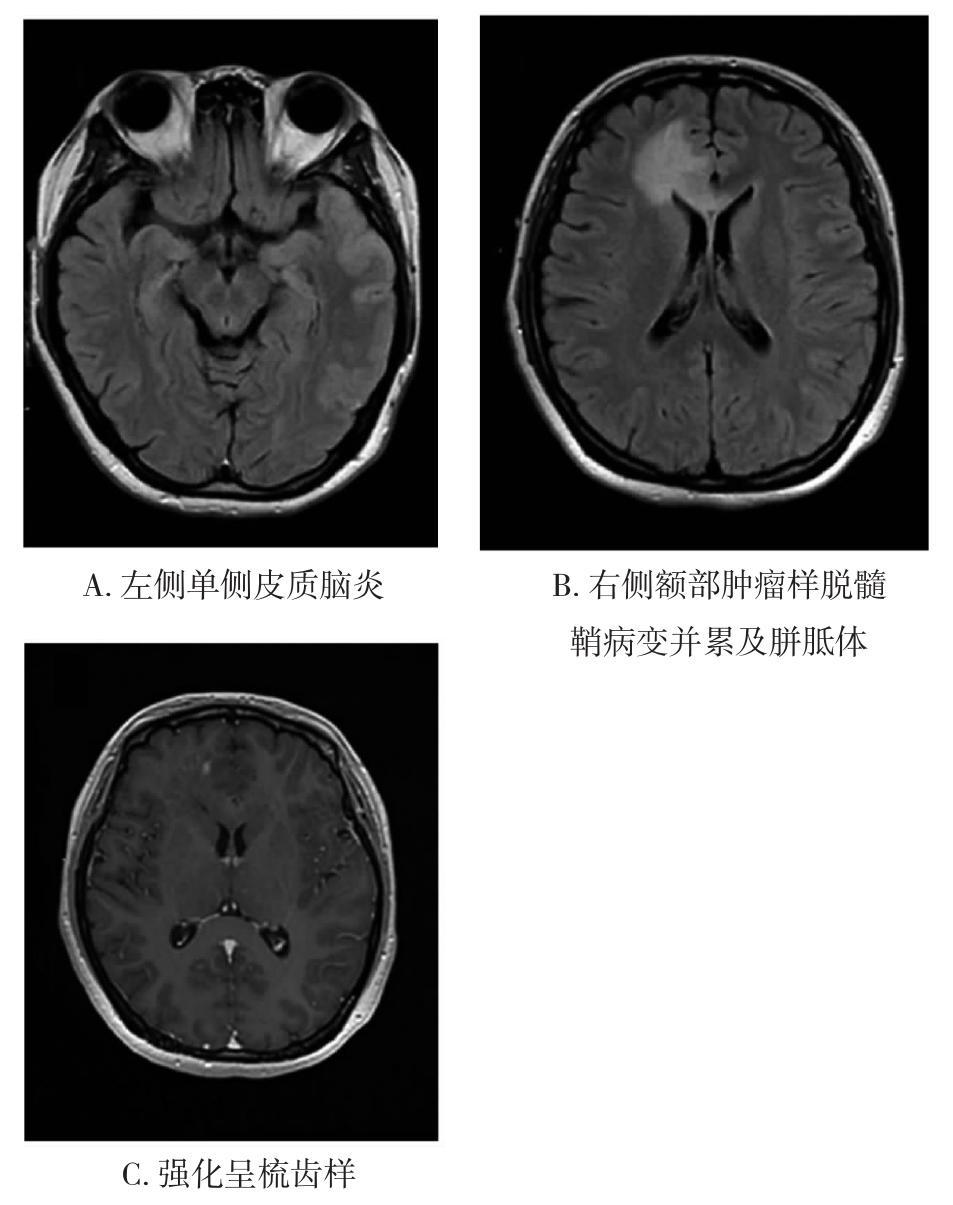

• 自身免疫性脑炎的诊断进展

2021, 46(7):754-759. DOI: 10.13406/j.cnki.cyxb.002867

摘要 (140) HTML (295) PDF 2.06 M (243) 评论 (0) 收藏

摘要:自身免疫性脑炎主要表现为急性或亚急性记忆障碍、精神行为异常及癫痫发作。2016年Lancet Neurolgy发表的自身免疫性脑炎临床诊断标准及排除标准及2017年中华医学会神经病学分会发布的《中国自身免疫性脑炎诊治专家共识》为我国自身免疫性脑炎规范化诊疗提供了重要参考。本文就临床常见的自身免疫性脑炎类型及近些年新发现的自身免疫性脑炎抗体相关综合征的临床特征作一总结,为自身免疫性脑炎的诊断提供思路。